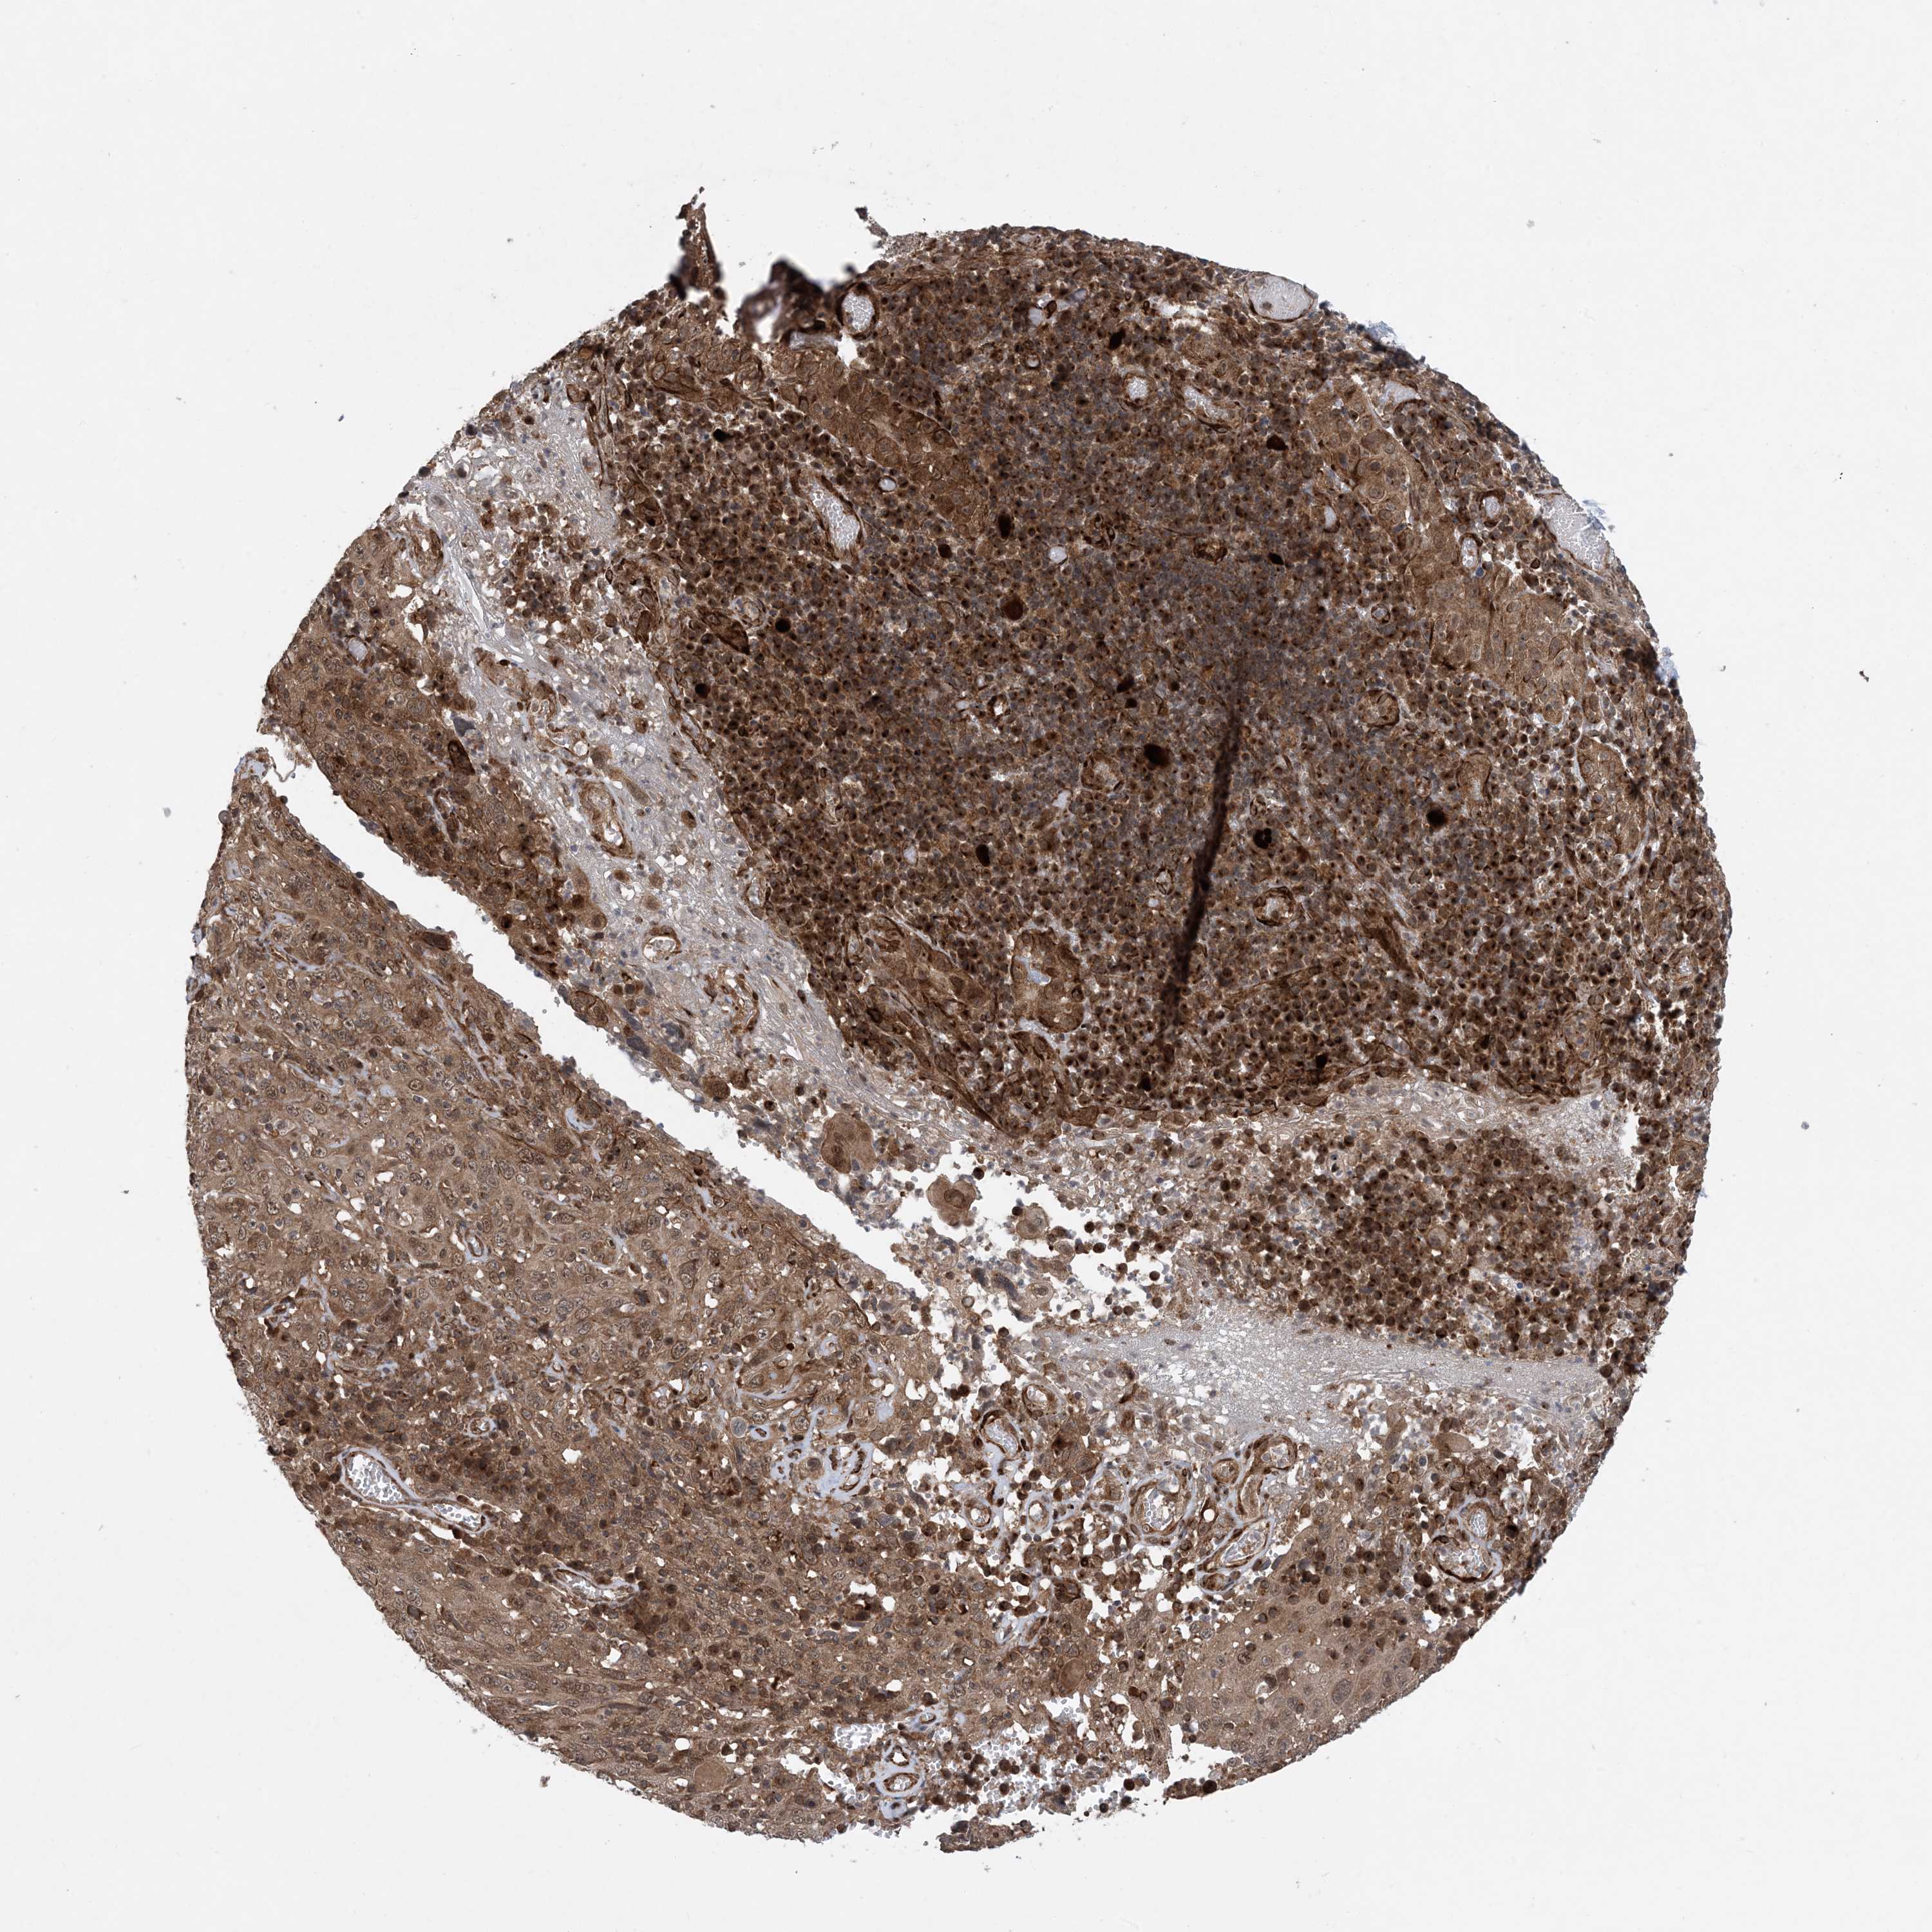

CERVICAL CANCER - Protein expressioni

A mouse-over function shows sample information and annotation data. Click on an image to view it in a full screen mode. Samples can be filtered based on level of antibody staining by selecting one or several of the following categories: high, medium, low and not detected. The assay and annotation is described here.

Note that samples used for immunohistochemistry by the Human Protein Atlas do not correspond to samples in the TCGA dataset.

Antibody stainingi

Antibody staining in the annotated cell types in the current human tissue is reported as not detected, low, medium, or high, based on conventional immunohistochemistry profiling in selected tissues. This score is based on the combination of the staining intensity and fraction of stained cells.

Each image is clickable and will lead to virtual microscopy that enables deeper exploration of all samples and also displays staining intensity scores, fraction scores and subcellular localization as well as patient and tissue information for each sample.

Antibody HPA034701

Antibody HPA034702

Staining

High

Medium

Low

Not detected

Intensity

Strong

Moderate

Weak

Negative

Quantity

>75%

75%-25%

<25%

None

Location

Nuclear

Cytoplasmic/membranous

Cytoplasmic/membranous,nuclear

Squamous cell carcinoma, NOS

Adenocarcinoma, NOS